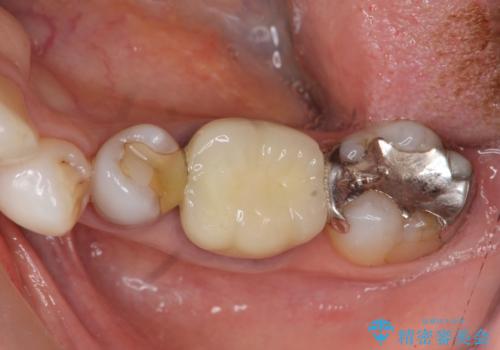

- 違和感や疼きのある左側小臼歯に加え全体的にクラウンや詰め物のやりかえを希望され来院されました。

治療後に再発した虫歯や根管再治療に加え、穴の空き症状のある上顎左側小臼歯は抜去を行いインプラントによる機能回復治療を計画します。

X線写真検査ではわからない虫歯も外してみると再発していることがあります。虫歯を丁寧に取り除き、再発を防ぐべく精密なクラウンの作製を行うことが長期的な予後につながります。